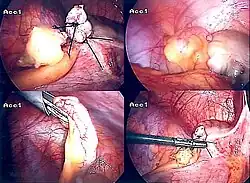

Laparoscopic appendectomy.

Laparoscopic view of a phlegmonous cecal appendix with fibrinous plaques, located in the right iliac fossa.

The surgical procedure for the removal of the appendix is called an appendectomy. A negative appendectomy constitutes the removal of a normal appendix with no sign of inflammation in histopathology examination. The prevalence of negative appendectomy varies but has been estimated to 13%.[76] Appendectomy can be performed through open or laparoscopic surgery. Laparoscopic appendectomy has several advantages over open appendectomy as an intervention for acute appendicitis.[91]

Laparoscopic appendectomy

Laparoscopic appendectomy was introduced in 1983 and has become an increasingly prevalent intervention for acute appendicitis.[95] This surgical procedure consists of making three to four incisions in the abdomen, each 0.25 to 0.5 inches (6.4 to 12.7 mm) long. This type of appendectomy is made by inserting a special surgical tool called a laparoscope into one of the incisions. The laparoscope is connected to a monitor outside the person's body, and it is designed to help the surgeon inspect the infected area in the abdomen. The other two incisions are made for the specific removal of the appendix by using surgical instruments. Laparoscopic surgery requires general anesthesia, and it can last up to two hours. Laparoscopic appendectomy has several advantages over open appendectomy, including a shorter post-operative recovery, less post-operative pain, and a lower superficial surgical site infection rate. However, the occurrence of an intra-abdominal abscess is almost three times more prevalent in laparoscopic appendectomy than open appendectomy.[96]